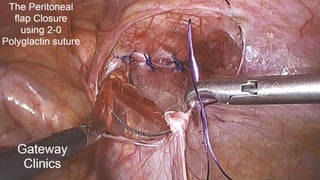

STEP 6 - The peritoneal closure

• A thorough closure of peritoneal incision or bigger peritoneal tears

should be achieved

• The peritoneum is closed by a running suture using a 2-0 vicryl

• Look - Mesh is not exposed now to abdominal organs

The peritoneum is closed by a running 2-0 vicryl suture

TIP – Far to Near